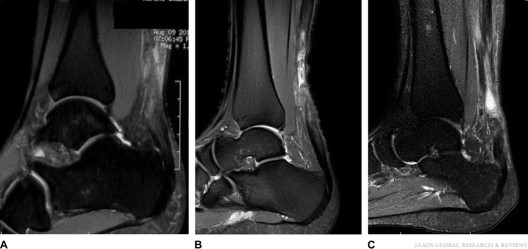

Magnetic resonance imaging (MRI) scan. While an X-ray gives doctors a clear view of bones, an MRI provides a better image of the soft tissues, such as tendons. The MRI can:

• Show the amount of tendon torn and the location of the tear.

• Help your doctor rule out a different injury that may have similar symptoms.

• Reveal if there was inflammation in the tendon prior to the tear.

These MRI scan images show a tear of the Achilles tendon at the middle part of the tendon. This is the most common site of Achilles tendon tear.

Reproduced from Hagen M, Pandya NK: Achilles Tendon Ruptures in Young Female Basketball Players: A Case Series. JAAOS Global Research & Reviews 2019; 3(6). Accessed July 2024.